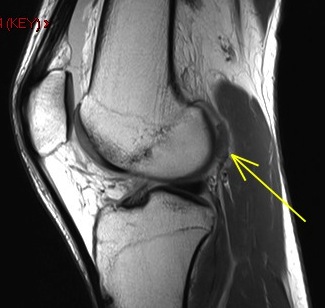

36 y/o was running and struck by car

Osteochondral fracture of the medial femoral trochlea. Notice the displaced chondral fragment behind the lateral femoral condyle interposed between the condyle and the posterior lateral capsule. Moral of the story – if you see an acute defect, look for the fragment.

Osteochondral fracture femur with displaced fragment